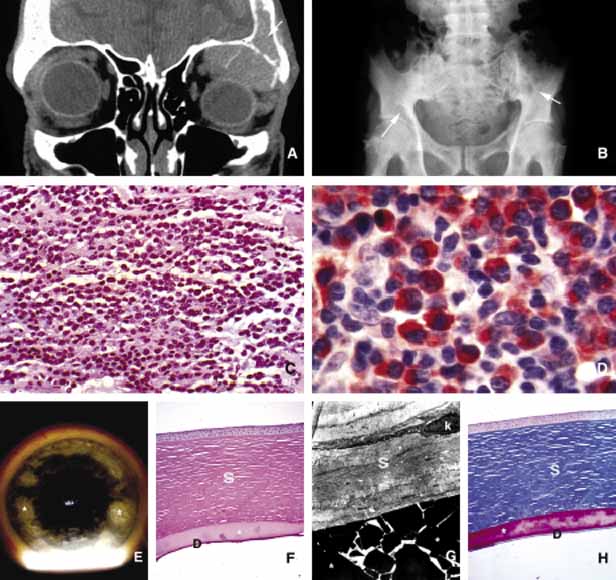

The traditional grouping of the primary vascular tumors in the orbit include capillary and cavernous hemangiomas, lymphangioma and arteriovenous malformations. The current thinking is that these lesions represent hamartomas that are made of different tissue components and may be better defined as “vascular hamartomatous lesions.”178 Histopathologic examination of these tumors often reveals mixtures of above listed tissue elements, the symptomatology, clinical course and response to treatment depends on the predominating histopathology. For example, if capillary hemangioma is the dominating element of a vascular tumor it is most often apparent at birth or within the first year, occurs in the anterior orbit and gradually regresses without any treatment. 179 Approximately 70% of capillary hemangiomas regress completely by 7 years of age. Patients with orbital capillary hemangioma may also have similar lesions in other organs. If systemic involvement is extensive, secondary thrombocytopenia known as Kasabach-Merritt syndrome develops. These lesions grossly appear as bright red, strawberry-like masses; histopathologically they are made of sheets of vascular endothelial cells with small lumen formations. Basement membranes surrounding these cells can be clearly identified with a reticulin stain. The predominating cell of the lesion is confirmed to be endothelial cell, by the positive staining for factor VIII, CD31 and CD34. The identification of an intracytoplasmic organelle known as Wiebel-Palade body by transmission electron microscopy also confirms the nature of the tumor cell as vascular endothelium (Fig. 16). For adnexal and orbital capillary hemangioma the treatment options include observation, intralesional and systemic corticosteroids, systemic interferon and in some cases surgical excision and radiation therapy.180–182

Fig. 16 Capillary hemangioma. A large capillary hemangioma occupying the periorbital skin, upper eyelid and superior and inferior anterior orbit. The eye is dislocated inferiorly by the large tumor occupying the lateral and superior orbit. Note the lack of bone involvement on the CT scan despite the very large size of the tumor. The light microscopic appearance confirms the tumor as capillary hemangioma with proliferation of endothelial cells forming clusters and abnormal capillaries, some of which are developed well enough to contain red blood cells. The transmission electromicroscopy demonstrates in Weibel-Palade (wp) bodies to confirm the nature of the tumor cell as capillary endothelium [N, nucleus].